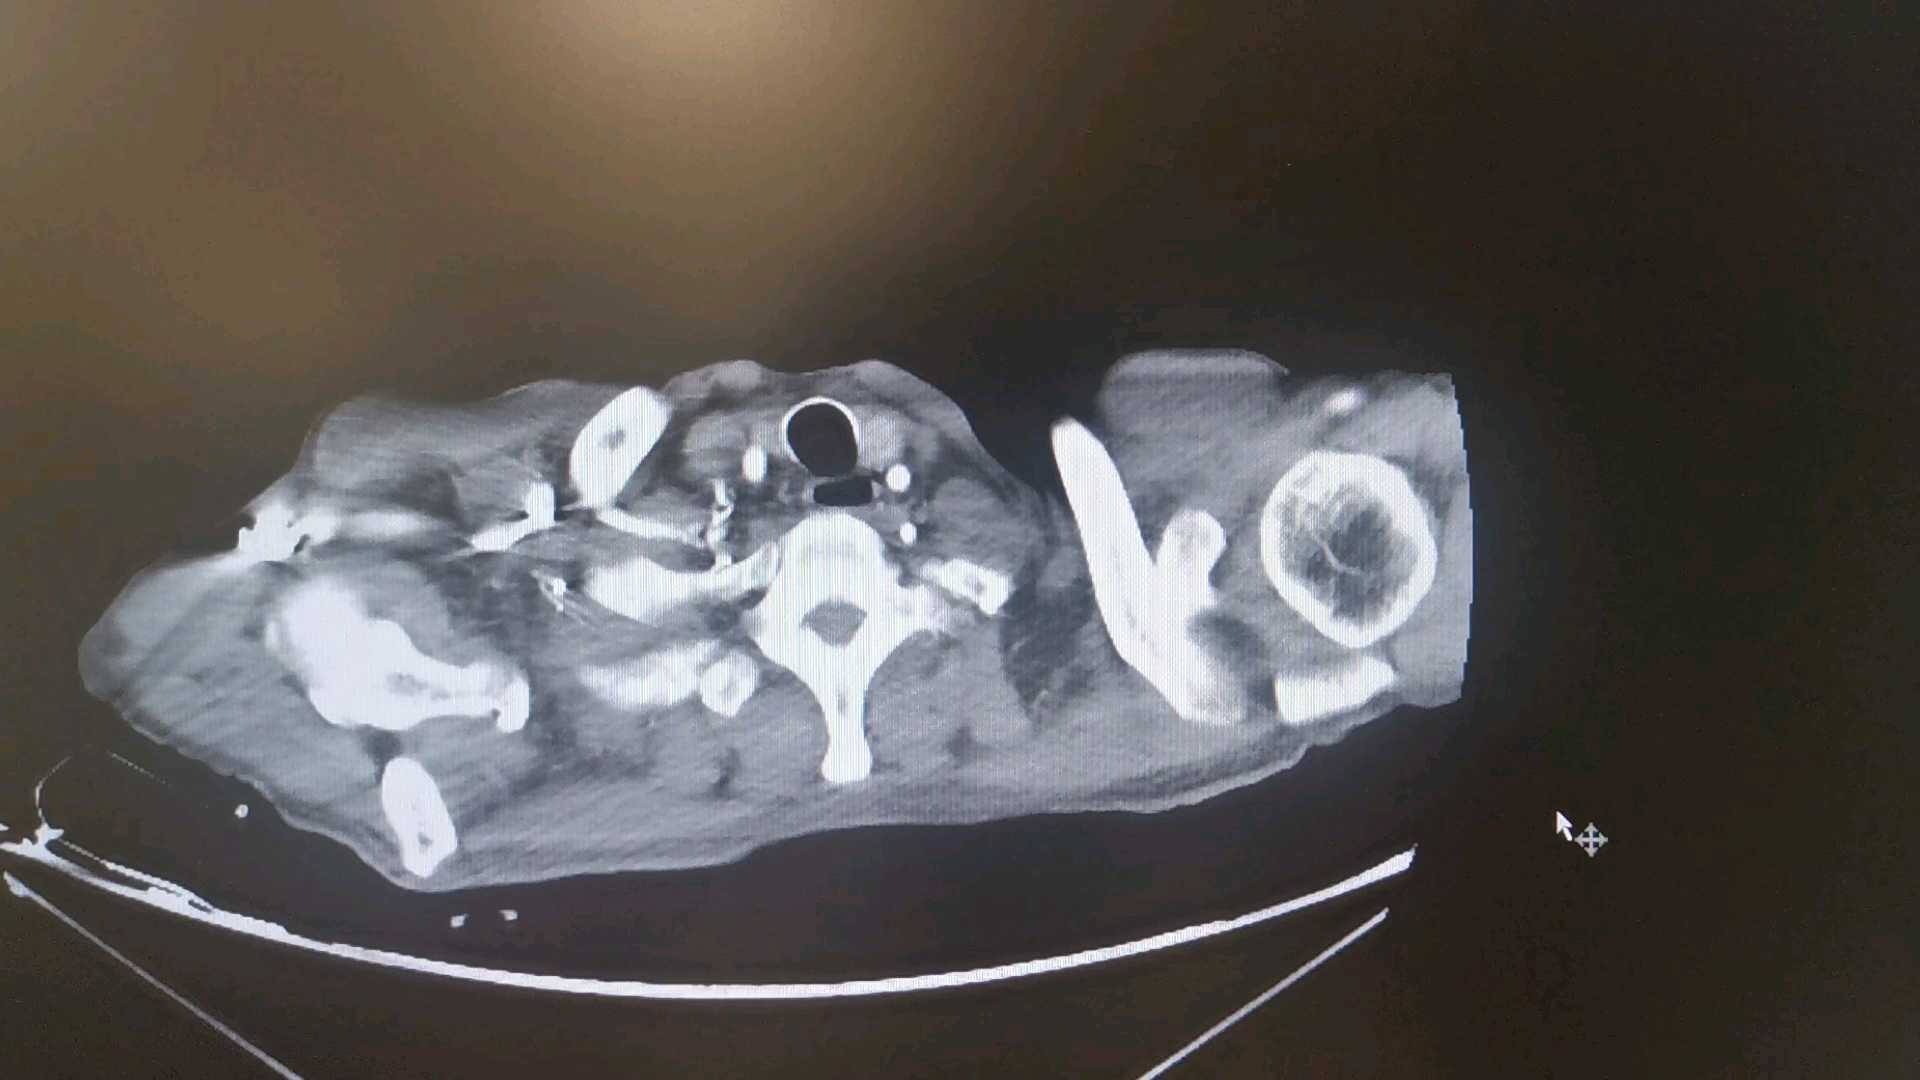

排除手木禁忌后行食管支架置入术,术后给予营养支持、补液、抗感染等治疗。11-17给予亚胺培南西司他汀钠1g q6h抗感染,同时给予静脉营养,持续心包引流,引流液为黄色脓性液体。11-17患者夜间出现频发房颤、室早,给予艾司洛尔泵入。11-18行心脏彩超示下腔静脉增宽,二尖瓣返流(轻度),三尖瓣返流(轻度),提示左室充盈异常,心包积液(少量)。心内科会诊建议继续抗感染治疗,复查血钾,艾司洛尔静脉泵入。心脏外科会诊示保持心包引流通畅,必要时行冲洗治疗,留取引流液行病原学检查;目前暂无拔管指征,待引流液性质清亮,连续2天小于50m可考虑拔管。11-20行增强CT检查: